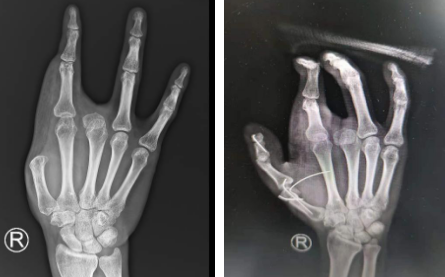

术前(左图)术后即刻(右图)

2021年4月,江师傅的家人陪着他再次从四川老家赶来,这一次,朱辉主任、滕医生手术团队为他进行了右拇指再造手术。术中取右足第一趾踇甲瓣+右足第二趾趾骨及关节,再造右拇指指骨及拇指指间关节,取髂骨填塞右足第二趾缺损骨质。手术非常顺利,术后江师傅无法下床,其父亲及医护人员细心护理,使他非常感动。谈及手术,江师傅表示,他在对比好几家医院之后,了解到朱辉主任带领的手外科实力强,服务好,所以便坚定选择了betway在线登陆手外科。他说,术后自己恢复很好,考虑以后再来做右手中指再造。